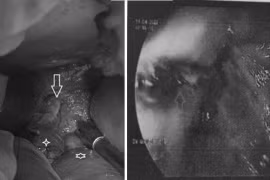

Hình ảnh thực quản trong nội soi dạ dày (bên phải) và lỗ thủng thực quản phát hiện khi phẫu thuật vùng bụng.

Vỡ thực quản sau nôn

Khoa Cấp cứu, Bệnh viện Nhân dân 115 (TPHCM) vừa cấp cứu một bệnh nhân 46 tuổi được chẩn đoán vỡ thực quản sau bữa nhậu buổi trưa.